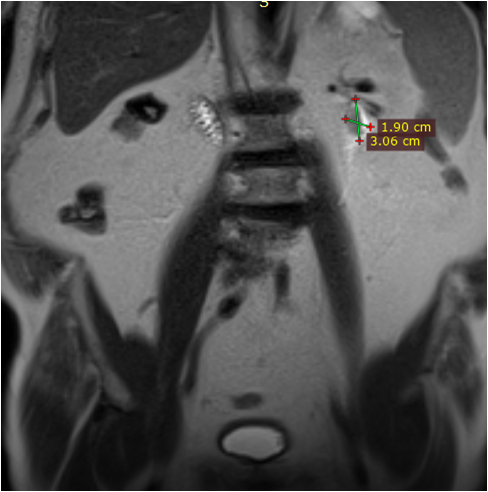

Під час проведення профілактичного УЗД у нього було виявлено пухлину правої нирки.

Основний: T-r (2 пухлини) правої нирки сT2 N0 M0 Gх ст ІI, кл.гр 2.

Супутній: Кісти нирок.